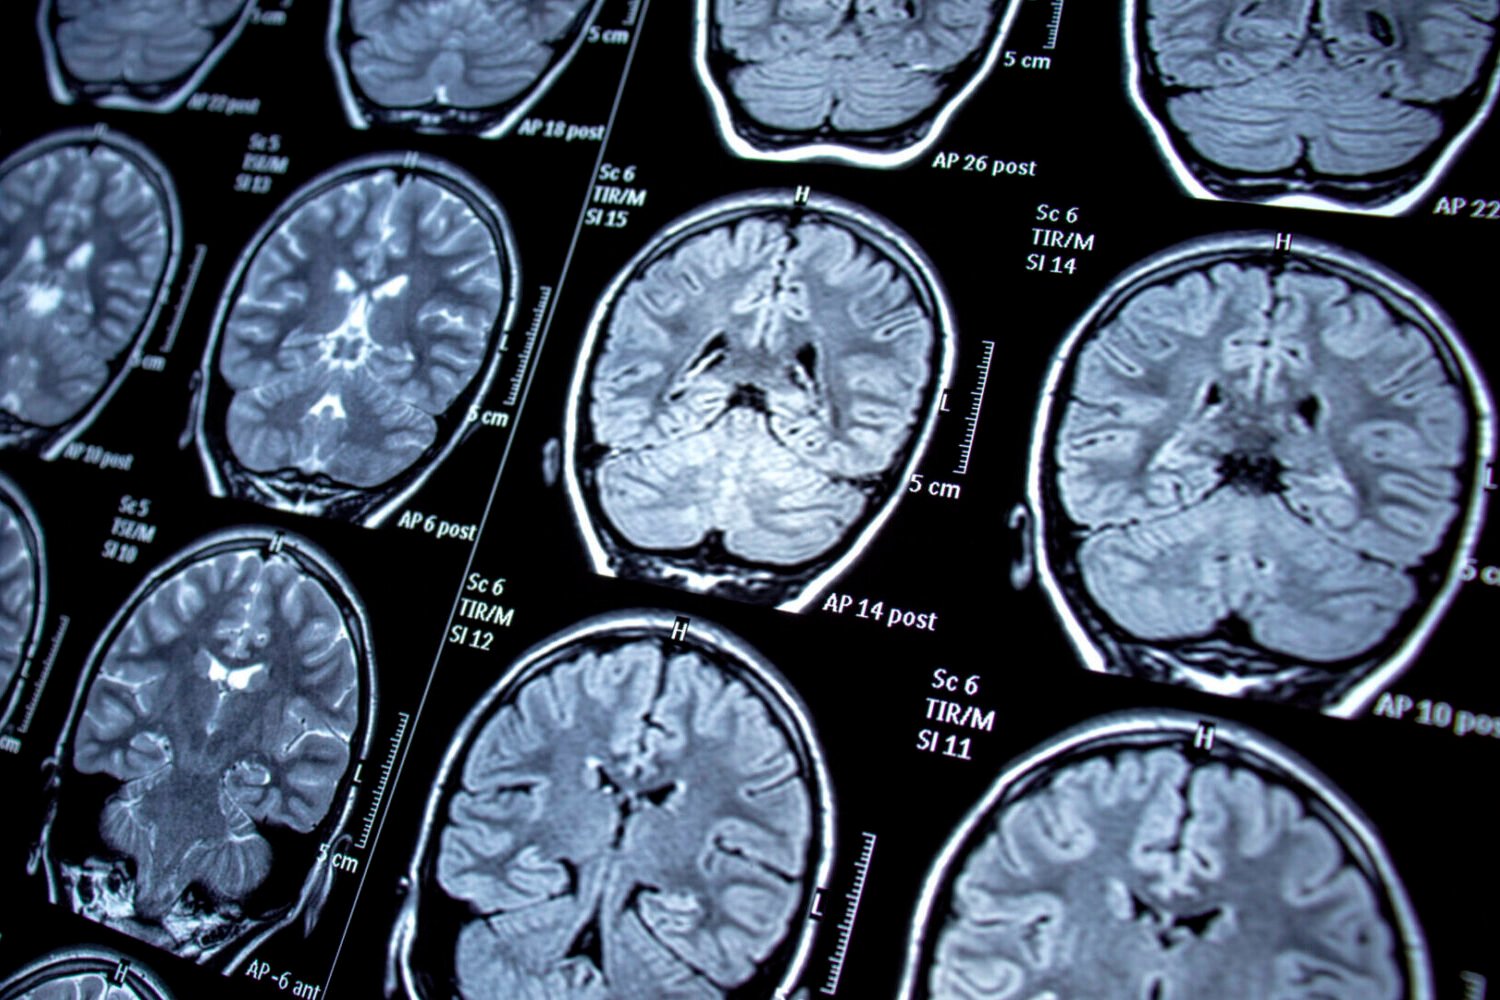

Some research has suggested that VSV and other germs hiding in the brain can cause subtle neurological harm, particularly an increased risk of Alzheimer’s disease and dementia. But this remains contentious and some studies have failed to support such a connection. Scientists at Brigham and Women’s Hospital led this newest study, hoping to better untangle any potential relationship between shingles and worsening brain health.